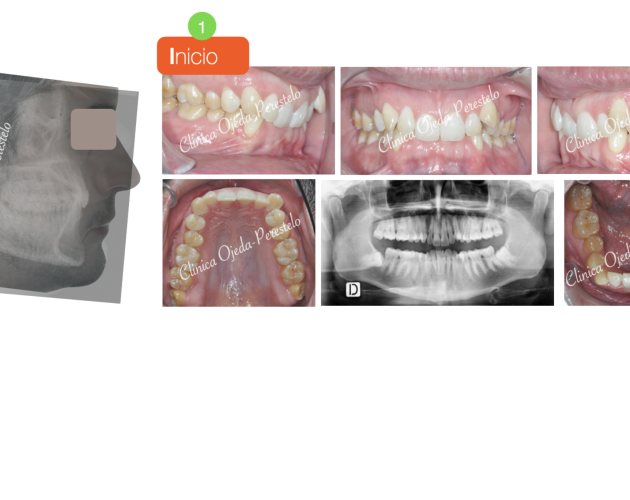

Mordida Abierta de molar a molar Casos de Éxito - Adultos

Clase II esquelética con Cirugía de Avance Md Casos de Éxito - Ortodoncia Plástica (Invisalign/Angel) - Adultos

Asimetría Facial en Clase III ósea y C.Ortognática Casos de Éxito - Mordida Cruzada - Adultos - Cirugía Ortognática

Clase III esquelética en dentición temporal Casos de Éxito - Niños

Clase II esquelética en niño con apnea moderada Casos de Éxito - Niños

Caso Ortodoncia Lingual Superior con Vestibular Inferior Casos de Éxito - Ortodoncia Lingual

Caso Multidisciplinar: Ortodoncia- Coronas sobre Implantes Casos de Éxito - Adultos - Casos Multidisciplinares

Caso Multidisciplinar: Ortodoncia-Implantes-Pónticos-Bioestética Casos de Éxito - Adultos - Casos Multidisciplinares

2ºMolar Mandibular Retenido Casos de Éxito - Dientes Retenidos

Caso Multidisciplinar: Ortodoncia-Implantes-Bioestética 11-21 Casos de Éxito - Casos Multidisciplinares

Caninos Maxilares Retenidos (13-23) + Bioestética 21-22 Casos de Éxito - Niños - Dientes Retenidos - Casos Multidisciplinares

Premolar Mandibular Retenido (35) Casos de Éxito - Niños - Dientes Retenidos

Clase II con Mordida Abierta Casos de Éxito - Ortodoncia Plástica (Invisalign/Angel) - Adultos

Clase II severa en Mandíbula Hipoplásica Casos de Éxito - Adultos - Cirugía Ortognática

Expansión Maxilar Asistida en Mord.Cruzada Casos de Éxito - Mordida Cruzada - Adultos - Cirugía Ortognática

Mordida Cruzada Unilateral con Apiñamiento Severo Casos de Éxito - Mordida Cruzada - Adultos

Mordida Cruzada Bilateral Casos de Éxito - Mordida Cruzada - Niños

Clase III esquelética en dentición definitiva Casos de Éxito - Niños

Mordida Cruzada con dolor Craneofacial Casos de Éxito - Ortodoncia Plástica (Invisalign/Angel) - Mordida Cruzada - Adultos

Clase III ósea severa con C.Ortognática Casos de Éxito - Mordida Cruzada - Adultos - Cirugía Ortognática

Asimetría Facial en Clase III ósea y C.Ortognática Casos de Éxito - Mordida Cruzada - Adultos - Cirugía Ortognática - Casos Multidisciplinares

Biprotusión esquelética con Sonrisa Gingival Casos de Éxito - Adultos - Cirugía Ortognática

Clase II osea de causa Md con Cara Larga Casos de Éxito - Adultos - Cirugía Ortognática

Clase II ósea con Resalte muy Aumentado y Extracciones dentarias Casos de Éxito - Adultos - Casos Multidisciplinares

Apiñamiento severo con molares con mal pronóstico Casos de Éxito - Adultos

Mordida Abierta Posterior con M. Cruzada en clase III ósea Casos de Éxito - Mordida Cruzada - Adultos

Clase III ósea tratada con Exo de cordales y Microtornillos Casos de Éxito - Mordida Cruzada - Adultos

Clase II con apiñamiento y sobremordida severa Casos de Éxito - Ortodoncia Plástica (Invisalign/Angel) - Adultos

Sonrisa gingival (encías) con Resalte Aumentado Casos de Éxito - Mordida Cruzada - Adultos

Clase III esquelética en dentición mixta Casos de Éxito - Niños

Canino Mandibular Retenido (33) Casos de Éxito - Dientes Retenidos

Mordida Cruzada y Abierta severa Casos de Éxito - Mordida Cruzada - Adultos

Ortodoncia-Implantes-Bioestética 22 Casos de Éxito - Ortodoncia Plástica (Invisalign/Angel) - Adultos - Casos Multidisciplinares

C Multidisciplinar: Orto Plástica + MASPE+ Corticotomías + Regen Casos de Éxito - Ortodoncia Plástica (Invisalign/Angel) - Mordida Cruzada - Adultos - Cirugía Ortognática - Casos Multidisciplinares

Mordida invertida en clase III (MARPE +Orto Plástica + elásticos Casos de Éxito - Ortodoncia Plástica (Invisalign/Angel) - Mordida Cruzada - Adultos